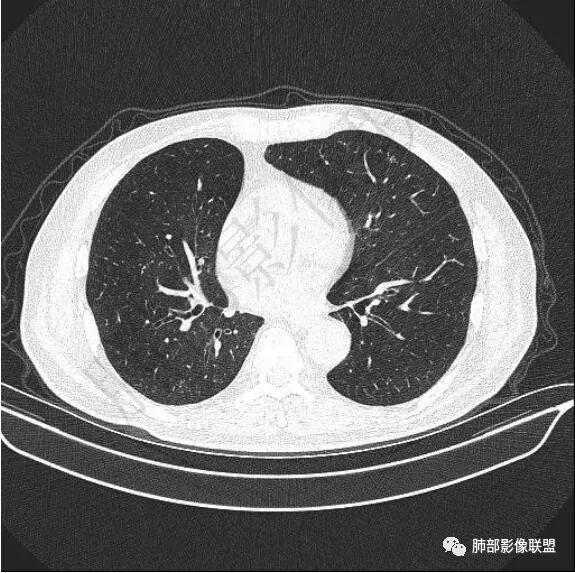

二..发现左肺上叶舌段实性密度小结节影,不规则略呈半环形,边界清楚,未见分叶、毛刺及磨玻璃晕。未见卫星病灶。

9个月后病灶明显增大,边缘较平直,部分膨隆,锁扣样外观,仍旧缺乏典型深分叶及张力,未见胸膜凹陷。

再1个多月后病灶继续增大,较明显不均匀强化,肺门一侧见低密度区。病灶边缘相对不清,可见毛刺。